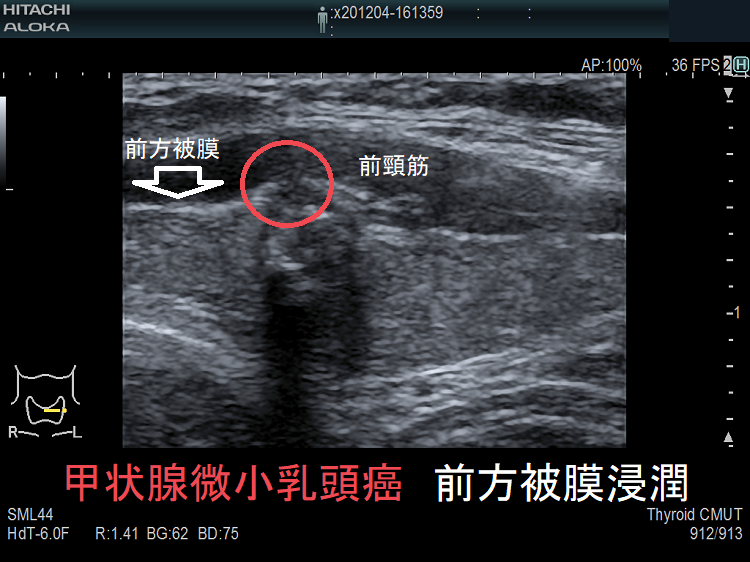

- 被膜浸潤した甲状腺微小乳頭癌 超音波(エコー)画像

ケース⑤ 甲状腺微小乳頭癌 僅かに前方被膜浸潤